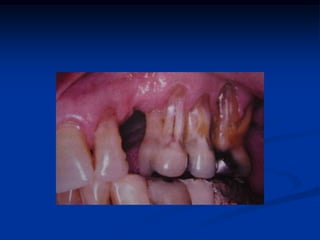

EXEMPLOS

Retirado de: Newmann, Takei e Carranza, 2004

• 30.

Retirado de: Newmann,Takei e Carranza, 2004